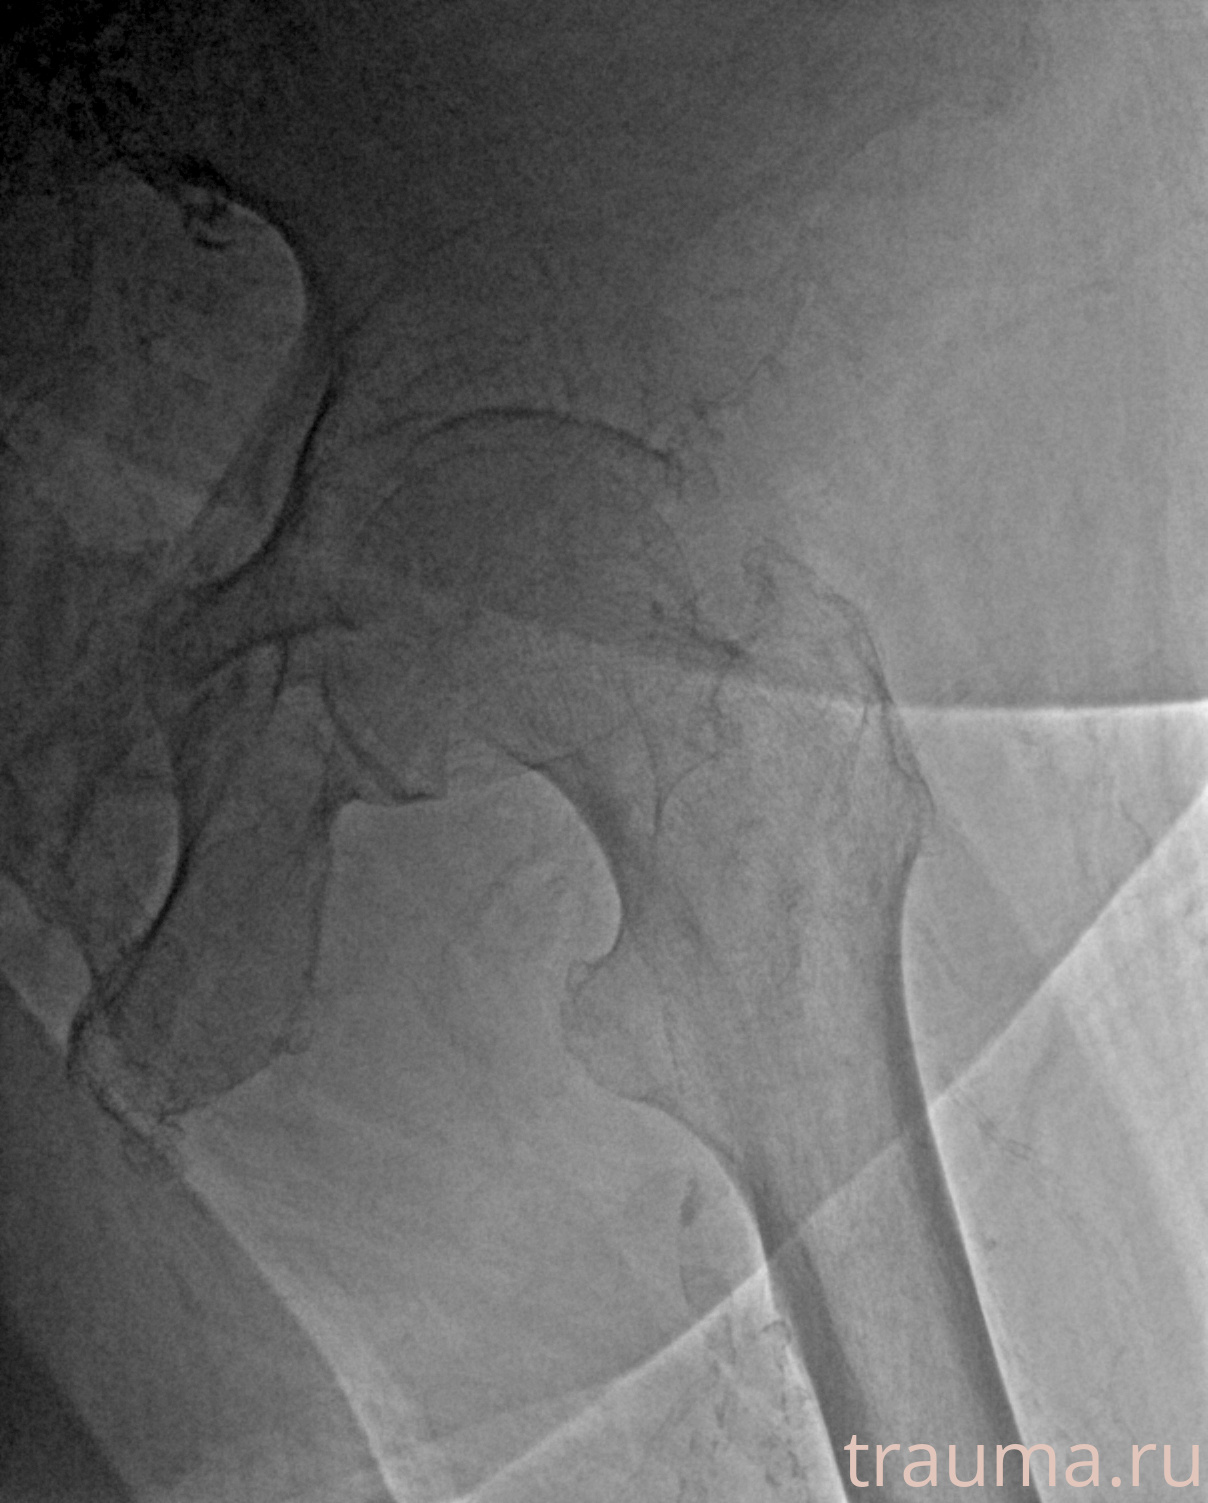

Рентгенограммы

Рентген на дому: по вашему адресу приезжает врач-рентгенолог, травматолог-ортопед с мобильным рентгеновским аппаратом, проводит диагностику травмы или заболевания, делает необходимые рентгенограммы, дает рекомендации по дальнейшему лечению. Получить качественные снимки в домашних условиях возможно благодаря уникальной методике, разработанной МосРентген Центром для института  Склифосовского